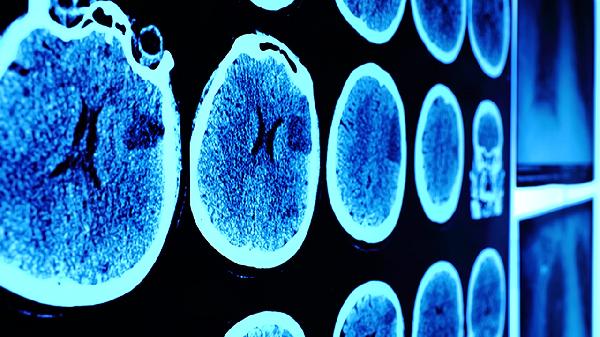

头部CT或核磁共振可排除颅内出血、颅骨骨折等器质性损伤。虽然脑震荡通常无结构性改变,但影像学能鉴别更严重的创伤性脑损伤。对于持续头痛或呕吐的患者,建议完善影像学评估。